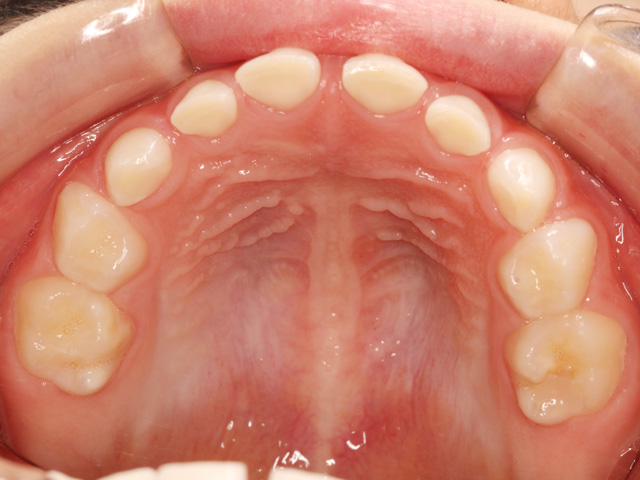

乳歯と永久歯が混在している段階を「混合歯列期(こんごうしれつき)」と専門的にに呼びますが、この段階で歯列不正があった場合に、顎の成長を活かしつつ歯並びの改善を同時に行う治療をこのように呼びます。